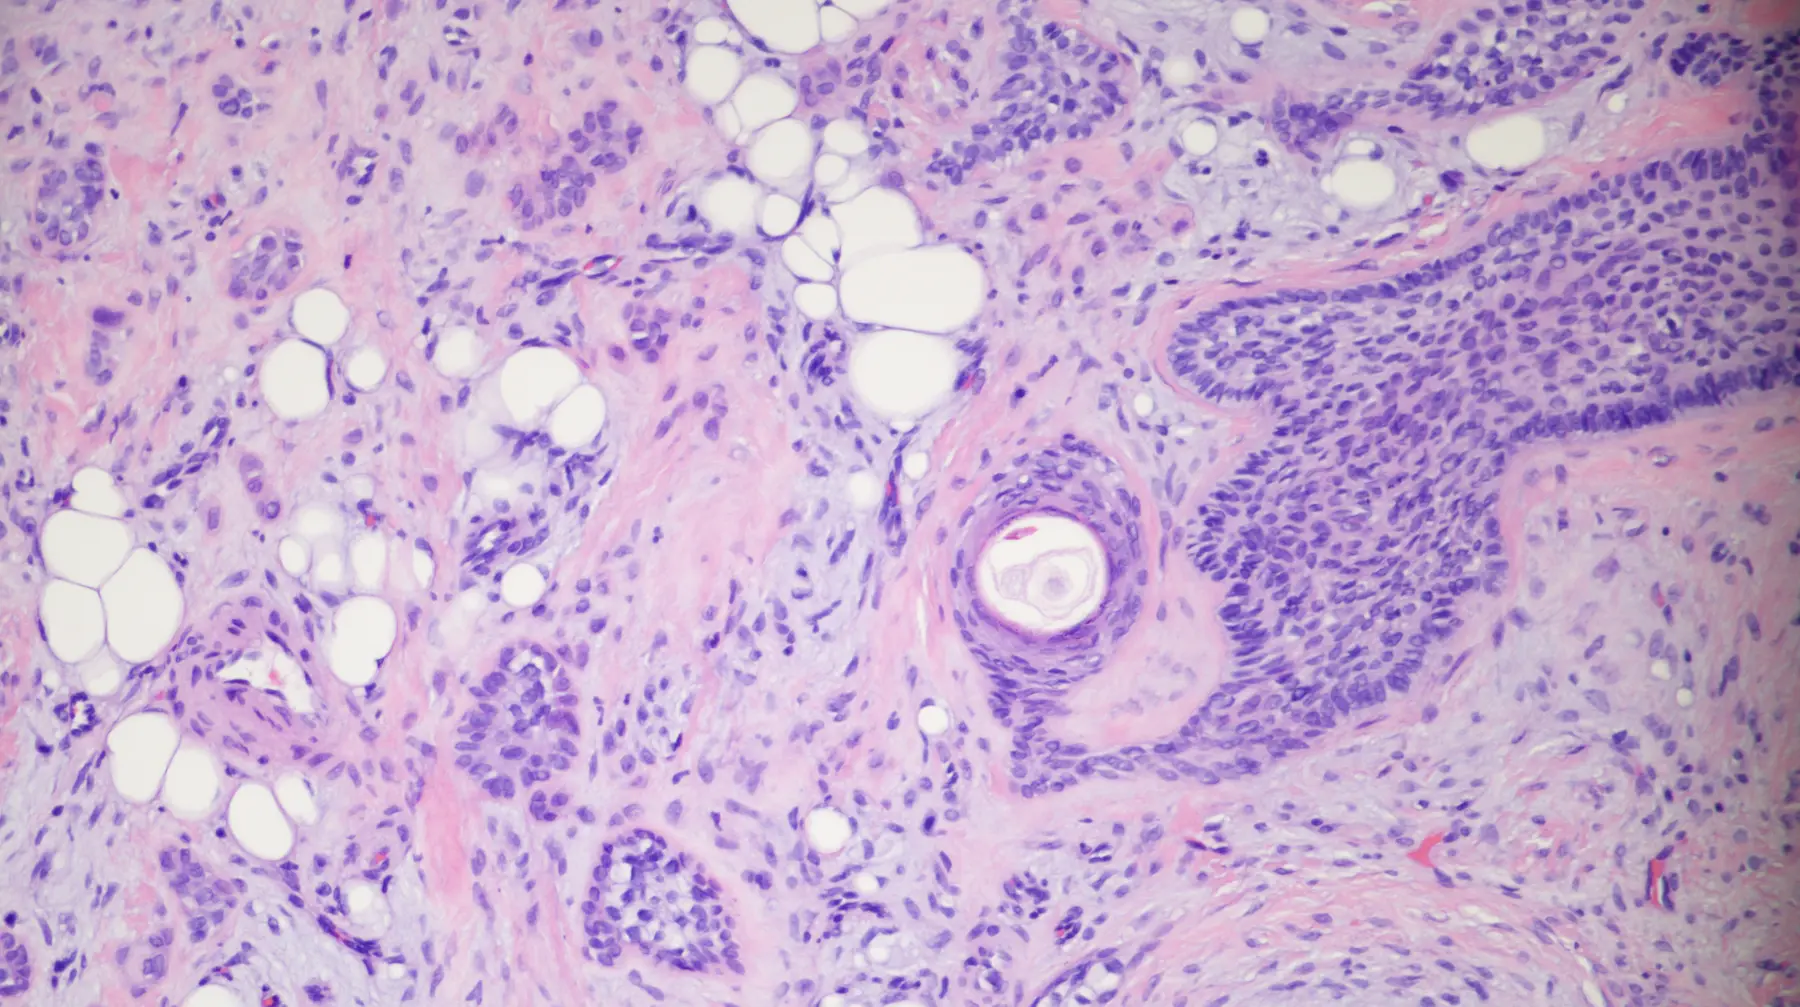

DermpathPro — CASE 4632